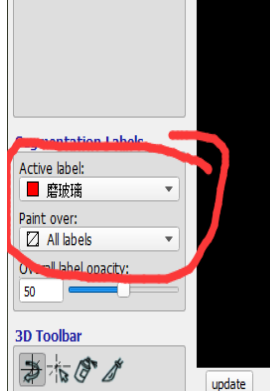

勾画对应病灶前,记得先选择病灶的类型label(软件左下角):Active Label

调整病灶的标签(比如,从磨玻璃 调整为实变)

如想将此标签从当前的磨玻璃改成实变,选择画刷模式,将Active label选为实变,将paint over选为磨玻璃,然后用笔刷涂抹即可修改

调整完后,切记将Active label选为你需要画的类型,将paint over恢复All labels